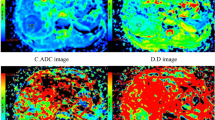

All images were analyzed by an abdominal radiologist (J.W. with 23 years of experience of liver MRI) on a workstation of the picture archiving and communication system. HCC was diagnosed based on the diagnostic criterion proposed by the American Association for the Study of Liver Disease (AASLD) in 2010 [22], i.e., wash-in in the arterial phase and washout in the delayed phase. All measurements were performed in consensus using vendor provided software (Functool on GE Advantage Workstation 4.6, GE Healthcare) by two trained radiologists (Q.G.S. with 3 years and R.H.Y. with 13 years of experience of liver MRI) who were blinded to the histological results, and further checked by the study coordinator J.W. After reviewing the DWI, T2WI and dynamic enhancement images, regions of interest (ROIs) were manually drawn on the axial b 1000 images to encompass as much lesion body as possible on the slice with the maximum tumor cross-section. ROIs were placed at least 5 mm away from the margin of the tumor to minimize partial volume effects [21]. Necrosis and hemorrhage were avoided by referring to T2WI images and dynamic enhancement on T1WI images [15, 23]. All the ROIs were transferred to ADC and IVIM-derived maps for measurement (Fig. 2). The area of ROIs ranged from 73 to 11,720 mm2 (mean area 1889 mm2).

A surgically confirmed moderately differentiated HCC in a 31-year-old man. A T2WI image, B diffusion-weighted image with b = 0, C–F ADC, D, D*, and f map, and G signal intensities vs. b-values. The mean values of ADC, D, D*, and f of the tumor were 0.91 × 10–3 mm2/s, 0.80 × 10–3 mm2/s, 17.6 × 10–3 mm2/s, and 21.6%, respectively